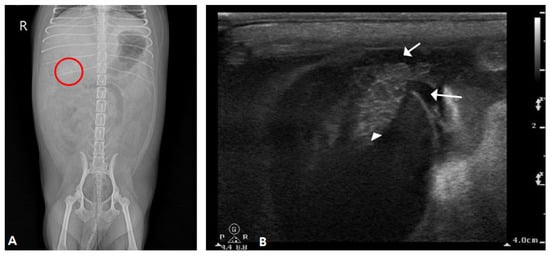

2.2. Case II